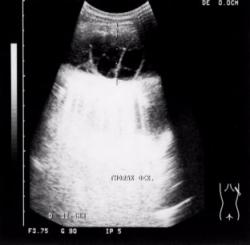

Рассмотрим пример экссудативного плеврита парапневмонической этиологии.

Пациент К, 1987 года рождения. Находился на лечении в пульмонологическом отделении с диагнозом: левосторонняя крупозная пневмония, левосторонний экссудативный плеврит.

На флюорограмме (Рис.4) определяется негомогенное, интенсивное затенение нижнего и среднего этажа левого легочного поля с косой четкой верхней границей по нижнему краю переднего отрезка III-го ребра. На фоне затенения не дифференцируется левая половина диафрагмы и левые реберно-диафрагмальные синусы.

Проведено ультразвуковое исследование плевральных полостей (Рис.5). В левой плевральной полости определяется не менее 500 мл свободной жидкости. Структура ее неоднородная с гиперэхогенной взвесью. Массивные фибринозные плевральные наслоения, расположенные между листками плевры. Базальные отделы левого легкого безвоздушные, по плотности сопоставимы с тканью селезенки.

Заключение: левосторонняя нижнедолевая крупозная пневмония в стадии опеченения. Левосторонний экссудативный плеврит.

Под контролем ультразвука проведена пункция плевральной полости. В процессе лечения жидкость в левой плевральной полости довольно быстро организуется с образованием фиброторакса, что подтверждается данными контрольного рентгенологического и ультразвукового исследований (Рис.6, 7). Левый синус облитерирован.